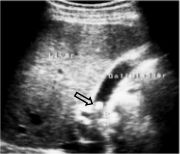

1- Echogenic focus in the gallbladder lumen (Picture 1),

Picture1. Echogenic focus in the gallbladder lumen.